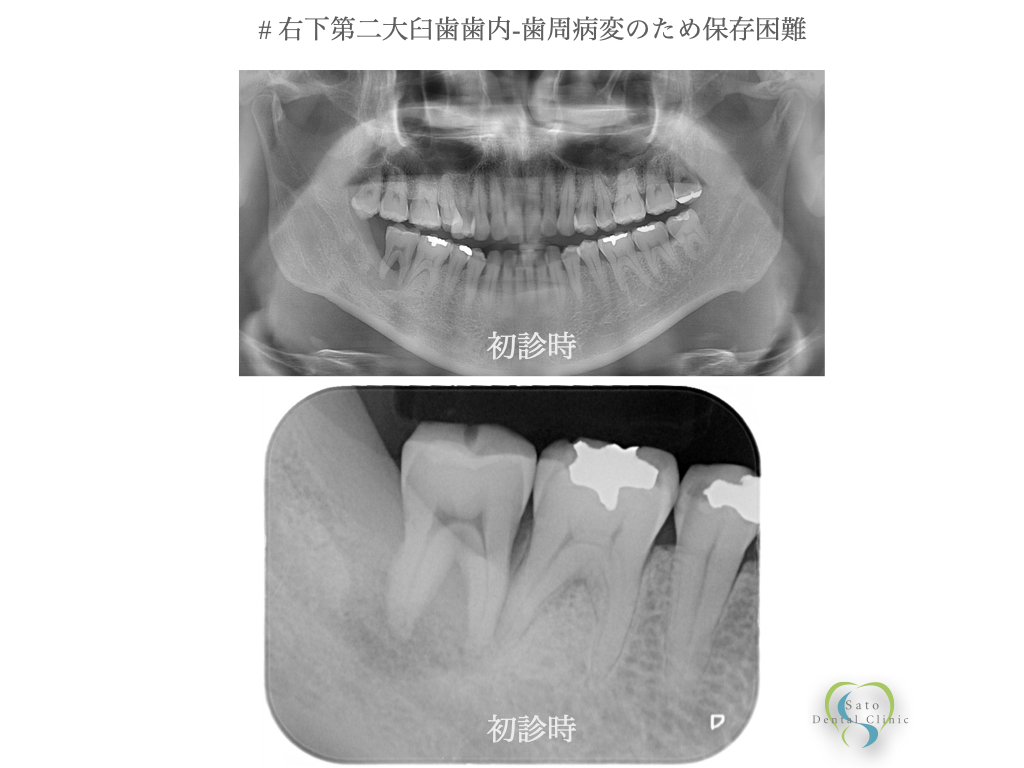

2026.03.12 【症例紹介】自家歯牙移植:親知らず活用できるかもしれません 歯の移植 Vol.114 皆様、こんばんは。さとう歯科クリニック院長の佐藤公麿です。 「歯を抜かなければならない」と言われたとき、多くの方はインプラントやブリッジを思い浮かべるかもしれません。 しかし、ご自身の歯を移植して失った歯を回復する「自家歯牙移...続きを読む